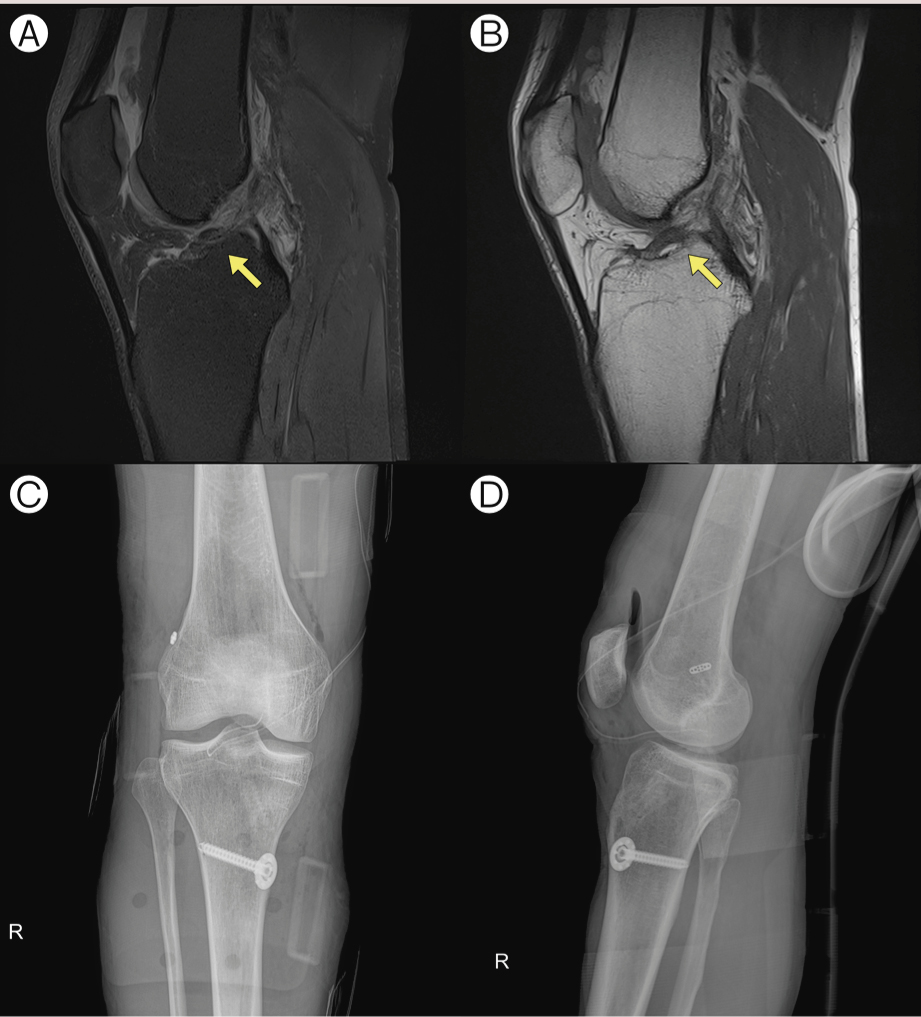

舌診상 舌質의 色이 淡紅하고 舌苔는 白했다. 목젖을 포함한 연구개가 전체적으로 충혈돼 있었고 반점이 관찰됐다, 비강 점막에도 역시 반점이 존재했다. 脈診상 양측 寸脈이 모두 弱했고, 양측 關脈은 沈한 모습을 보였다. 상복부 초음파 검사상 특이 소견은 관찰되지 않았다(그림1).

1.jpg

그림1. 한의사의 내과 진료실을 내원한 외국인 환자의 상복부 초음파 검사